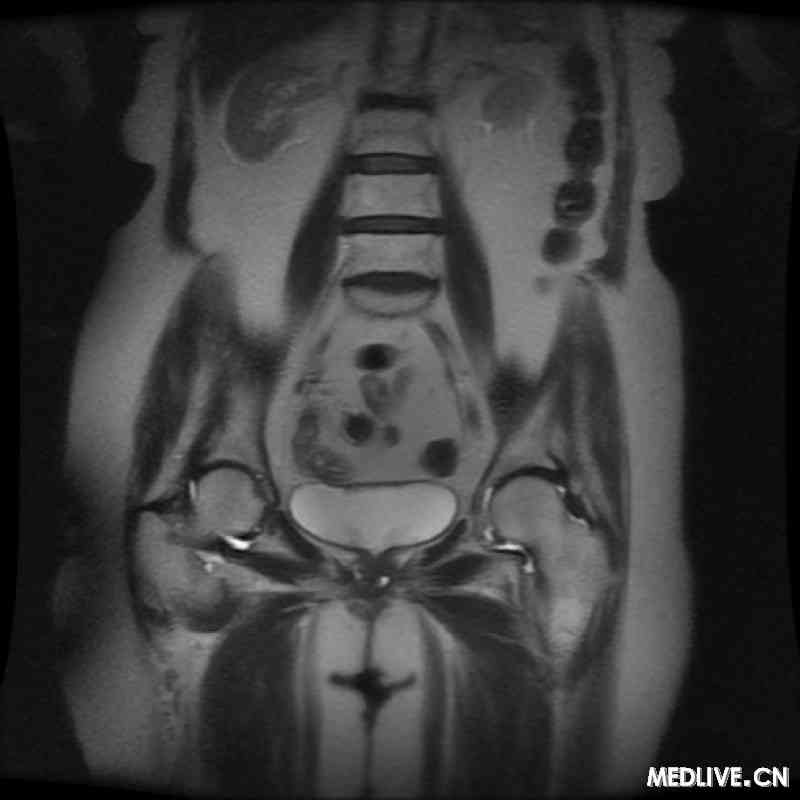

患者女性,81岁,主诉耻骨上疼痛,尿道内有分泌物,伴尿频、尿急、尿不尽。既往病史包括因外阴癌行外阴切除术,非何杰金氏淋巴瘤经环磷酰胺治疗后缓解,有吸烟史,每年40包。体检发现尿道7点钟方向处有一坚硬肿块,有触痛。磁共振(MRI)检查结果显示尿道两侧病灶处均有液体充盈,见图1。膀胱镜检查结果呈阴性。

图1 盆腔MRI检查结果显示两处独立的尿道憩室